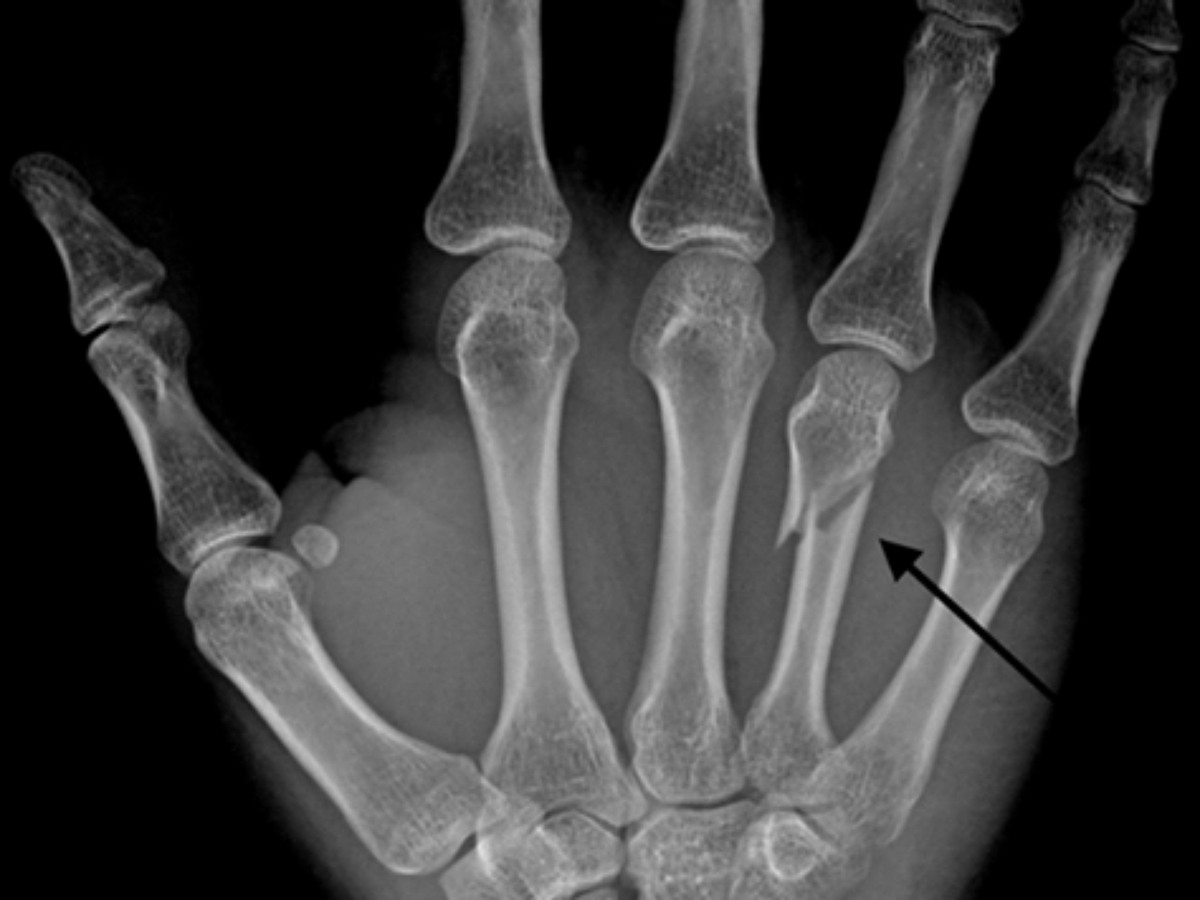

Roy Nelson exibe fratura em raio-x de sua mão

A vitória por nocaute contra Rodrigo Minotauro rendeu mais do que a redenção e o bônus de "Melhor Performance da Noite" a Roy Nelson. Na luta principal do UFC de Abu Dhabi, no último dia 11 de abril, o americano também voltou para a casa com a mão fraturada. A potência dos golpes que o "gordinho do UFC" aplicou no brasileiro acabou resultando numa lesão.

O peso-pesado publicou a imagem da fratura em suas redes sociais. Na verdade, o americano já tinha uma suspeita, mas só após uma ida ao médico pôde confirmar a existência da lesão. "Finalmente fui ao médico. Está quebrada, mas às vezes é isso o que acontece quando você soca tão forte", publicou o lutador.